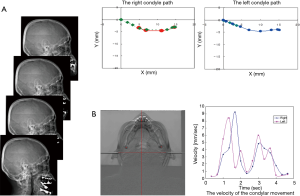

Initially, we developed a kinetic X-ray imaging technique and a functional analysis method to quantitatively assess the movement of the temporomandibular joint (TMJ) (Figure 2) (4,5). This joint was chosen because of the high prevalence of TMJ disorders, particularly among young individuals, and the lack of quantitative evaluation in diagnosis and treatment in such cases (6). This system is useful in TMJ screening examinations and diagnostic observations, and preoperative informed consent because it is easy to understand anomalies on dynamic radiographs. Although other studies have reported attempts to assess the TMJ using tracking systems with optical markers and MRI because these are considered as diagnostic examinations, they are expensive, complex to use, and require a long examination time; as a result, they have not been successfully used in clinical practice (7,8).